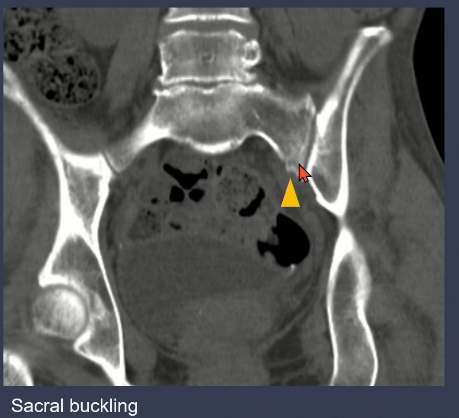

3. LC type